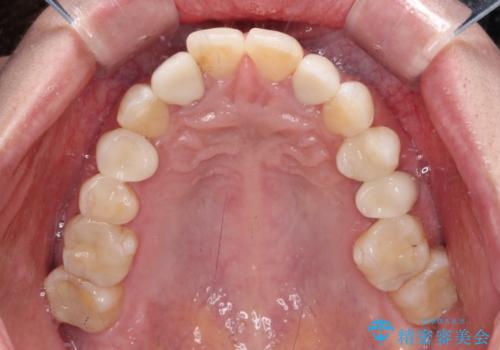

- クラウンから金属の土台が見えてきてしまったとのことで、作り替えを希望して来院された患者様です。

前歯や金属が露出している歯、痛みを感じる歯を中心に、オールセラミッククラウンにて補綴治療することとしました。

以前はセラミッククラウンのフレームとして金属が使用されており、歯肉の経年変化やセラミックのすり減りなどにより、金属が見えるようになってくることがあります。

現在は金属の代わりに強化セラミックを使用したオールセラミッククラウンが主流です。金属色が気になる方はご相談ください。